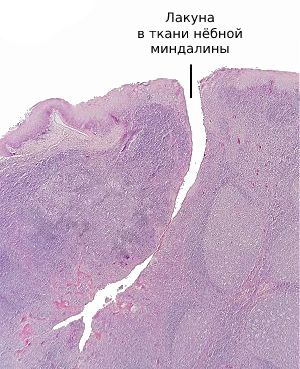

К развитию паратонзиллярного абсцесса предрасполагает сложное строение нёбных миндалин: они состоят из множества углублённых карманов (лакун), которые расположены в толще ткани и визуально напоминают фьорды.

Глубина лакун может достигать двух-трёх сантиметров. Их поверхность выстлана железами Вебера, которые механически очищают миндалины во время артикуляции, жевания и сжимания миндалин мышцами глотки при глотании, что можно сравнить с выжиманием рукой поролоновой губки.

![Лакуна в ткани нёбной миндалины [11]](/pimg3/luchevaya-diagnostika-abstsessa-B28134A.jpeg)

Снижение иммунитета, заражение патогенными бактериями, чаще всего бета-гемолитическим стрептококком, рубцы нёбных миндалин при длительном хроническом тонзиллите приводят к закупорке выводного протока желёз Вебера. Воспалительный отёк не позволяет продуктам жизнедеятельности бактерией и погибшим лимфоцитам выйти наружу в ротовую полость. В результате в ближайшей к нёбным миндалинам рыхлой клетчатке скапливается гной, который не может адекватно выйти наружу [9] [12] .